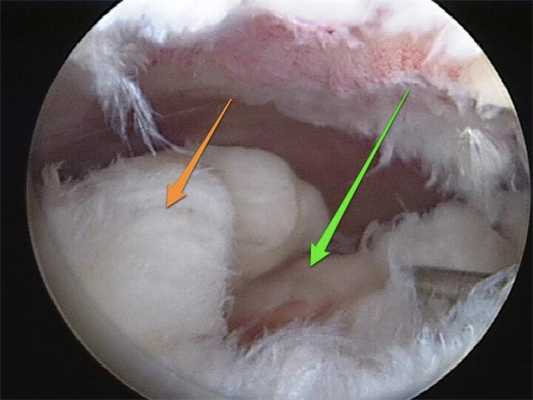

• Травмы циклопа:

о Очаговая фиброзно-синовиальная ткань в передней межмыщелковой вырезке

о На артроскопии определяется «голова» с центральной областью нарушения пигментации; отсюда вытекает название травма циклопа